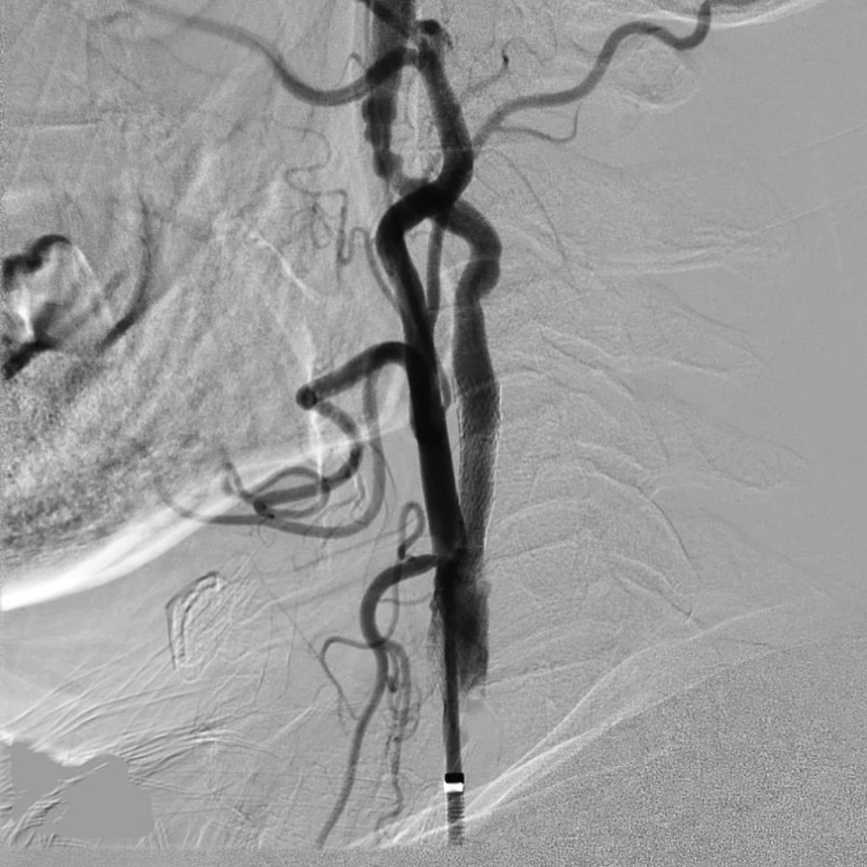

脑保护:Filterwire保护伞的规范使用

选用伞与导丝一体的Filterwire保护伞(on-wire设计),操作要点:导丝尖端柔软,轻松通过狭窄病变;在远端颈内动脉平直段释放保护伞,确保完全贴壁,有效拦截术中脱落的斑块。

预扩张与支架植入:匹配病变特点的器械选择

预扩张:使用5/30mmAviator球囊,扩张前需将患者心率提升至80次/分以上(避免扩张时迷走神经反射导致心率骤降);

支架选择:选用8/40mmPRECISE开环支架,其柔顺性好,适合迂曲的颈动脉解剖结构,定位精准且完全覆盖病变。

保护伞回收:避免斑块脱落的关键细节

释放后观察到保护伞内可能捕获斑块,回收时先收至一半(避免挤压导致斑块溢出);

因支架为开环设计(存在倒钩、毛刺),回收装置通过支架时需轻柔,可通过旋转尾端或调整患者头位避开阻碍,严禁蛮力操作。